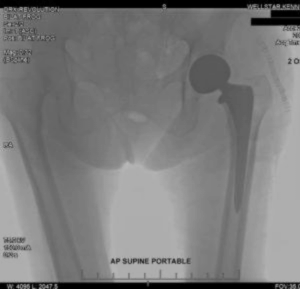

Carolyn broke her femur in the fall. Doctors determined she needed a hip replacement surgery to repair it. Because of her age, she spent several months after the surgery recovering in a rehabilitation facility. She made a good recovery but now walks with a cane and is not as active and mobile as she used to be before her injury. Her medical bills from the surgery and rehabilitation were over $80,000.